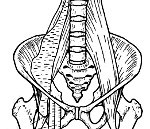

Подвздошно-поясничной мышцей называют анатомическую структуру, которая располагается в подвздошной ямке, включает в себя большую подвздошную мышцу, поясничную мышцу и окружающую их фасцию. Воспалительный процесс в этой структуре развивается при лимфогенном, реже гематогенном или контактном проникновении инфекционных агентов в толщу мышцы. В качестве возбудителя обычно выступает золотистый стафилококк, реже - стрептококк, энтерококк, синегнойная или кишечная палочка. Основными причинами илеопсоита считаются:

Лечебная тактика определяется стадией процесса. При серозном воспалении назначают массивную антибиотикотерапию. При формировании абсцесса лечение только хирургическое - вскрытие и дренирование. Производят срочное вскрытие с использованием люмботомического или внебрюшинного косого разреза (по Пирогову). После удаления гноя полость тщательно исследуют пальцем для обнаружения затеков. При необходимости выполняют дополнительные разрезы в поясничной области или на бедре. В рану устанавливают резиновую трубку, иногда осуществляют аспирационное дренирование. В послеоперационном периоде применяют антибиотики и общеукрепляющие средства, проводят дезинтоксикационную терапию.